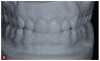

Fig 7. A man presented with significant tooth surface loss and a desire for an esthetic smile makeover but with minimally invasive treatment and as little tooth preparation as possible.

Figure 7